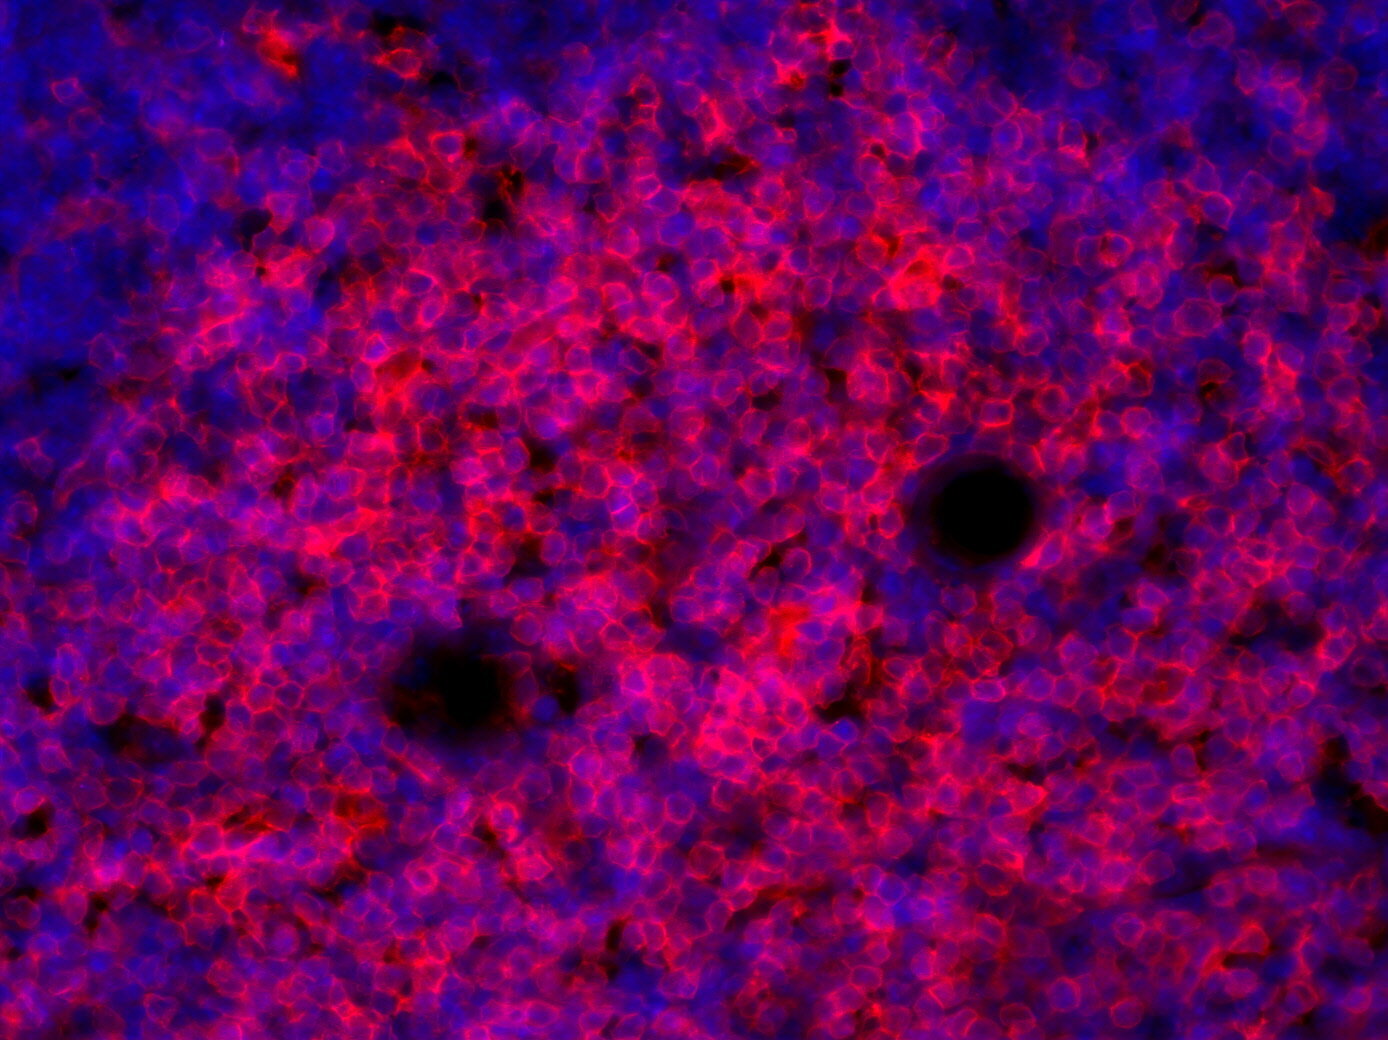

IHC: 1 : 100 gallery

IHC-Fr: 1 : 100 gallery

Immunohistochemistry (IHC) on 4% PFA perfusion fixed tissue with 24h PFA post fixation. Immunoreactivity is usually revealed by fluorescence or a chromogenic substrate. Some antibodies require special fixation methods or antigen retrieval steps. For details, please refer to the ”Remarks” section.

Immunohistochemistry on fresh frozen (IHC-Fr) cryo-tissue-sections. In contrast to standard PFA perfusion fixed tissues, fresh frozen cryo-tissue-sections can be variably postfixed with alcohols, acetone or PFA. Alcohol or acetone fixation is e.g. of advantage for antigens masked by PFA crosslinking. For recommended postfixation, please refer to the ”Remarks” section. Immunoreactivity is usually revealed by fluorescence or a chromogenic substrate.

IHC: Antigen retrieval with citrate buffer pH 6 is required.

IHC-Fr: The following fixatives are possible: methanol, 4% formaldehyde/PFA